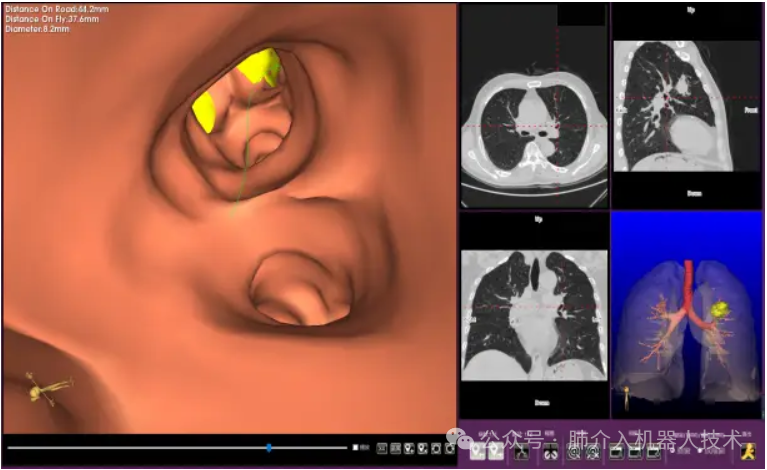

03、奧泰康助力肺部穿刺手術(shù)導(dǎo)航系統(tǒng)獲證

2024年1月31日,經(jīng)國(guó)家藥品監(jiān)督管理局公示,蘇州朗開醫(yī)療技術(shù)有限公司自主研發(fā)的肺部穿刺手術(shù)導(dǎo)航系統(tǒng)(國(guó)械注準(zhǔn)20243010222)獲得NMPA批準(zhǔn)上市,奧泰康助力本項(xiàng)目注冊(cè)申報(bào)服務(wù),系2024年奧泰康助力獲得的首張三類醫(yī)療器械注冊(cè)證。